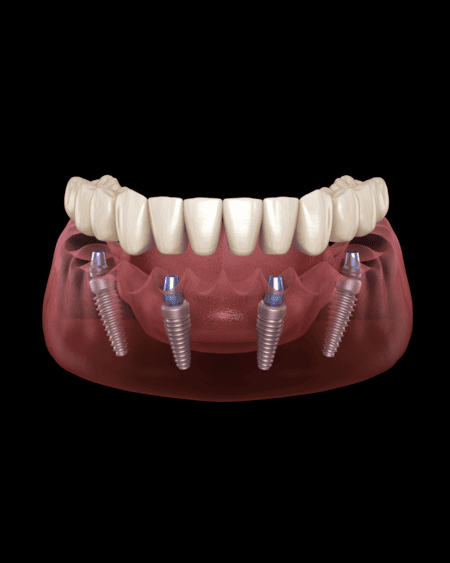

All-on-4 Implants:

These are full mouth implant-retained dentures. They are used when all the teeth in one jaw are missing. The dentist will place an average of four or more implants in your jaw and fit an implant-retained denture to it. You can find out more in our guide to getting All-on-4 implants abroad.